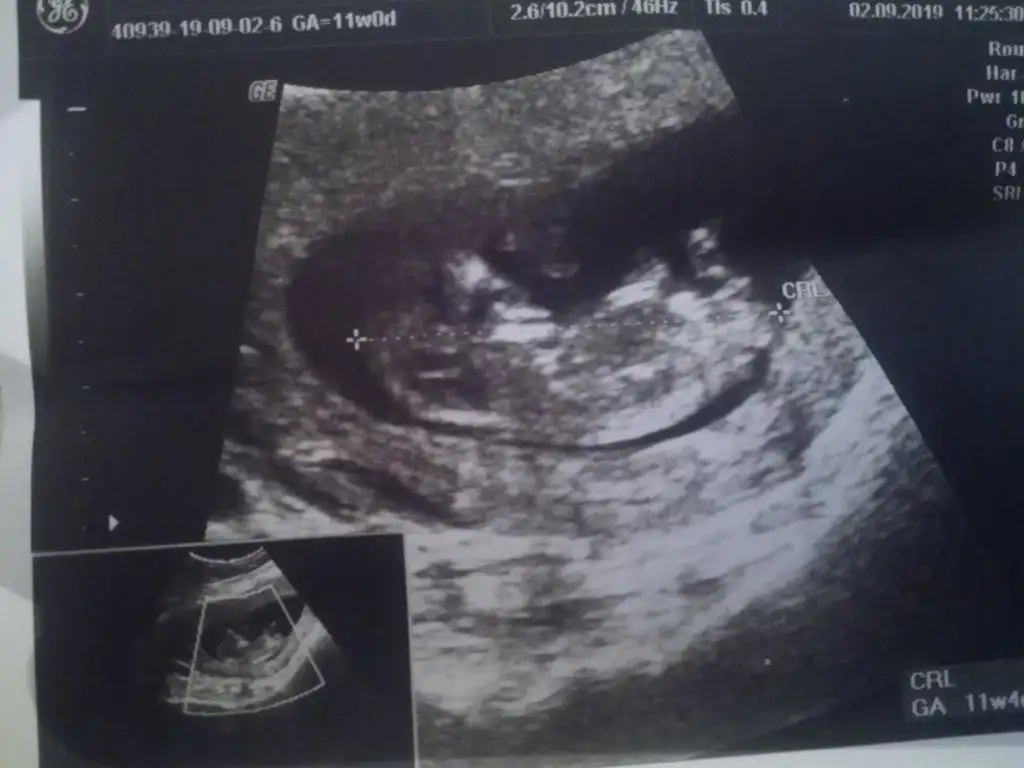

Kız gibiMerhaba hanimlar gecen hafta yazmistim nub icin 11 sonrasi daha iyi olur demistiniz bugunde kontrolden geldim cikar mi bi tahmin acaba❤

Dr daha iyi goruyor ama bu usg ye gore KizzzMerhaba hanimlar gecen hafta yazmistim nub icin 11 sonrasi daha iyi olur demistiniz bugunde kontrolden geldim cikar mi bi tahmin acaba❤